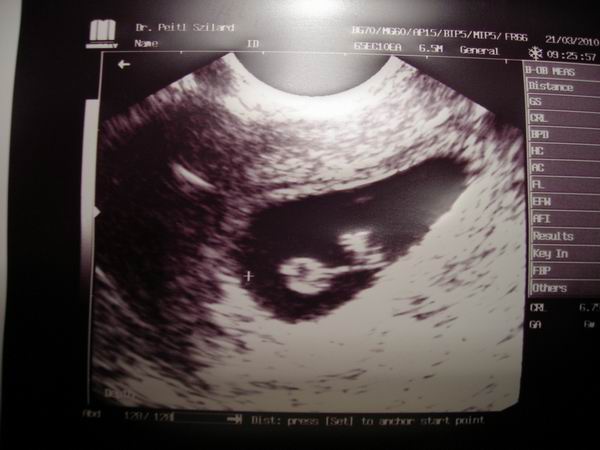

Szal minden rendben! Petezsák szép, kicsi embrio ott lesett a sarokban, de még tényleg csak egy kis sejtés volt! Így szívhangot még nem lehetett egyértelműen detektálni, bár a doki már látni vélte. 5+3-n voltam.

2 hét múlva megyek újra, addigra megígérte a doki ,h lesz szívhang.